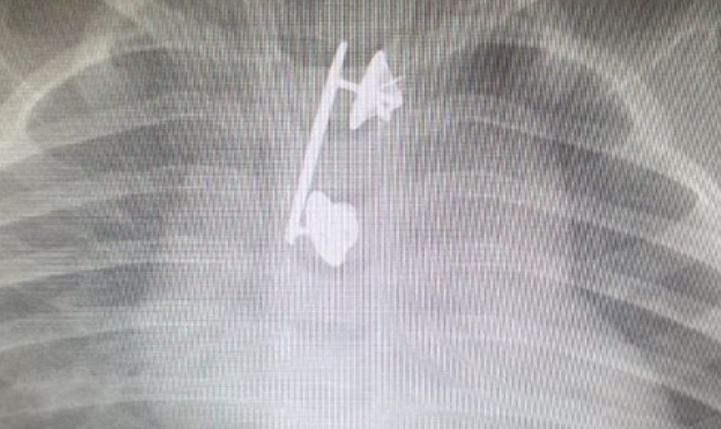

סיכת המ"מ של הקצינה נמצאה בוושת של בנה הפעוט

זוג הורים, קצינים בצה"ל, הבהילו לאחרונה את בנם בן ה- 10 חודשים לבית החולים 'קפלן' אחרי שחש ברע, התקשה בפעולת הבליעה ואף הקיא דם. לאחר צילום רנטגן הרופאים גילו: סיכת...